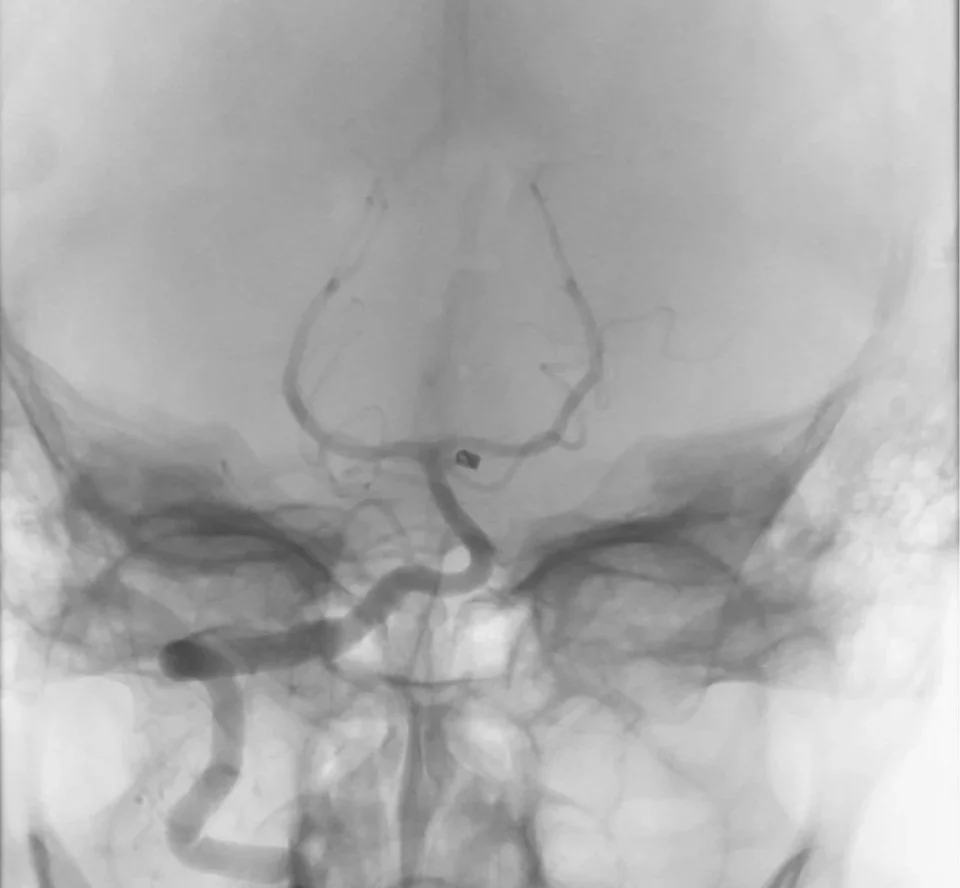

The company is developing both off-the-shelf and custom vascular models designed to replicate challenging tortuosity, complex anatomy, and highly reproducible practice environments for physicians and industry partners.